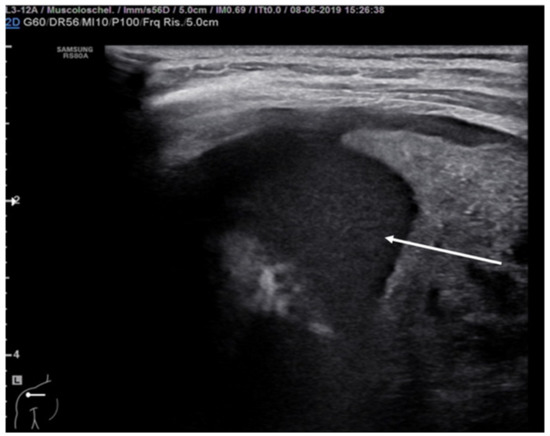

The lung abscess appears as a well-demarcated capsular structure surrounding a hypoechoic core without internal vascularity on color Doppler (Figure 11). Furthermore, it is possible to distinguish lung abscess from pyopneumothorax through the presence of all four specific signs: air-fluid level, synchronous movement of air-fluid levels with breaths, loss of gliding sign above the air-fluid level and the suspended microbubble sign (punctate hyperechoic pinpoints with shadows that move more or less randomly with respiratory movement within the pleural effusion) [56,57].

Figure 11.

Hypoechogenic capsule lesion with irregular, hyperechogenic edges suggestive of lung abscess (white arrow).